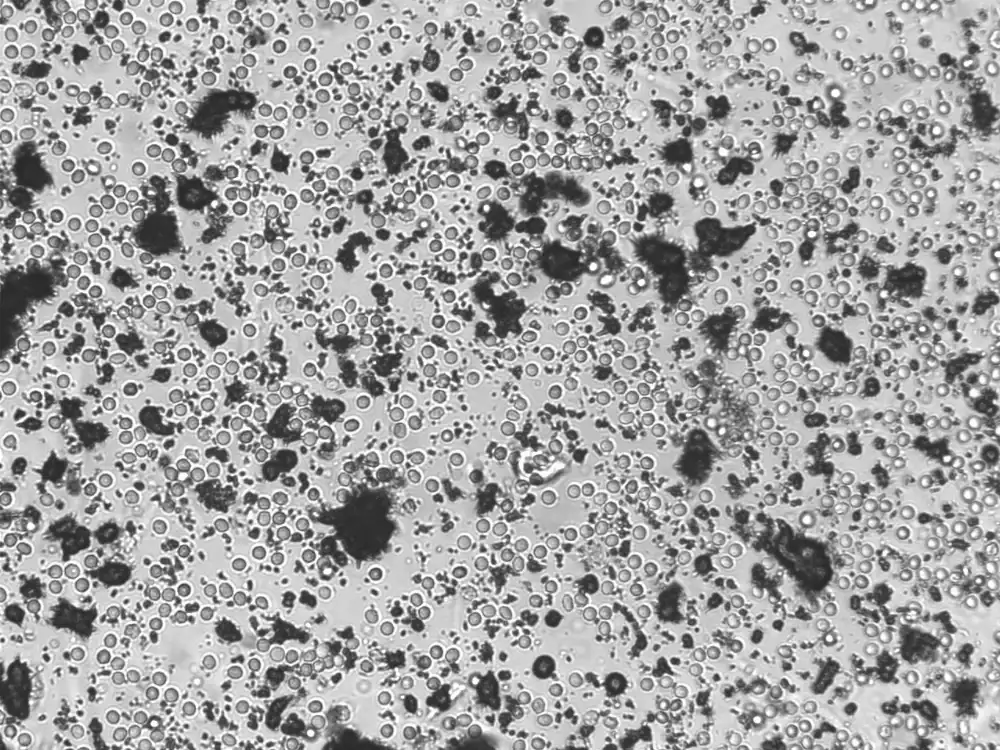

Ammoniumuraatkristallen zijn zeldzame kristallen die voorkomen in alkalische of neutrale urine, meestal bij aanwezigheid van ammoniak, geproduceerd door urease-producerende bacteriën zoals Proteus of Ureaplasma. Ze hebben een kenmerkend uiterlijk: geel- tot bruingekleurde, bolvormige structuren met stekelige uitsteeksels (“doornen”). Deze kristallen ontstaan vaak in urine die langdurig heeft gestaan, of in urine met een hoog ammoniakgehalte, bijvoorbeeld bij een urineweginfectie. Ze vertonen sterke birefringentie onder gepolariseerd licht, maar zijn klinisch meestal van geringe betekenis. Visueel kunnen ze worden verward met onder andere leucinekristallen, die eveneens geelbruin zijn, maar een radiaal, concentrisch patroon vertonen zonder uitsteeksels.

Overzicht